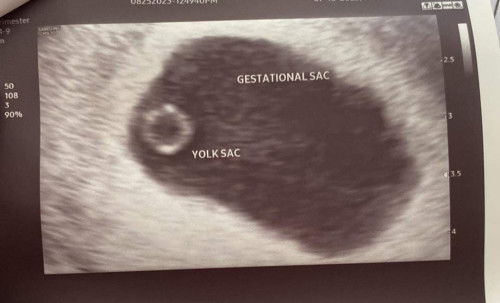

5W5D Pregnancy

Hello mga mamsh. first time mommy here, ask ko lang kung merong kaparehas ko. 5weeks and 5days at the time of TVS last september 08 with gestational sac and yolk sac. pinababalik ako this september 22 for follow up TVS. hoping and praying na makitang nag develop sya and may heart beat na. ask ko lang din if possible na walang pregnancy synptoms bukod sa breast tenderness at medyo pagpait ng panlasa?

same, 6 weeks naman ung akin, Ges Sac at Yolk sac lang nakita. take mo lang po yung vitamins mo para mag tuloy tuloy yung pag grow ni baby. 28 weeks na kami today ❤

wla po bang heartbeat sa first tvs nyo po? 5W5D din po ako ngpa TVS and nka indicate naman with heartbeat